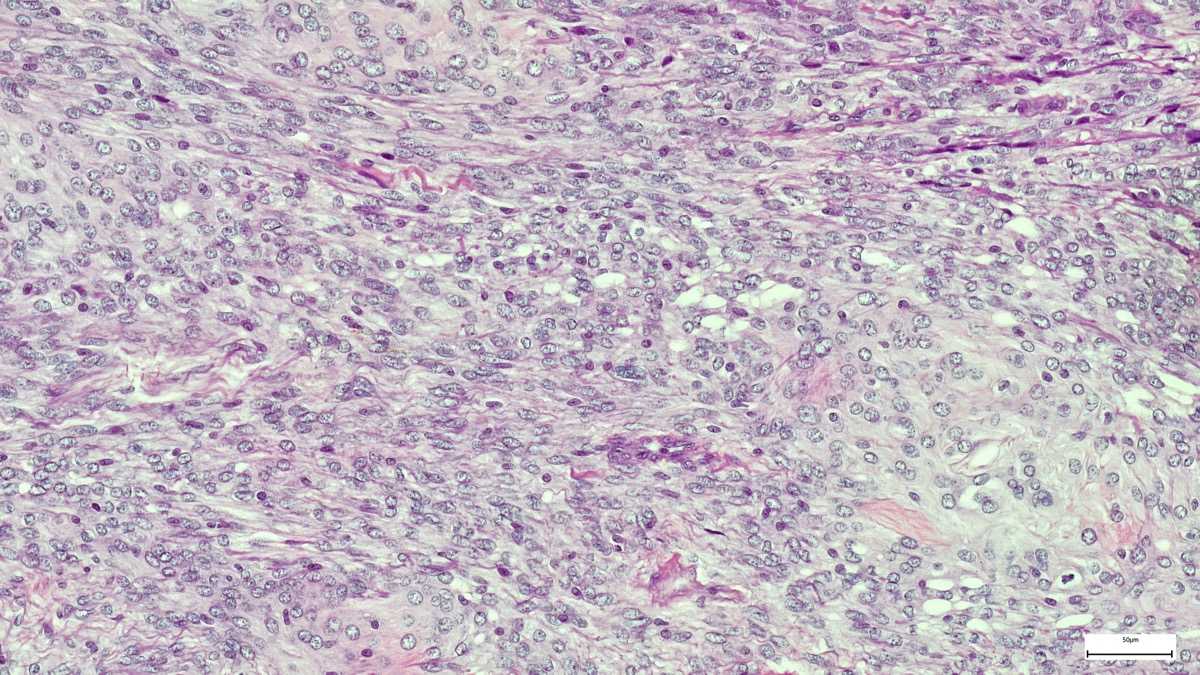

Molecular and Genomic Profiling of Head and Neck Tumors

- PI: Richard V. Smith, MD

- Sponsor: Montefiore Einstein